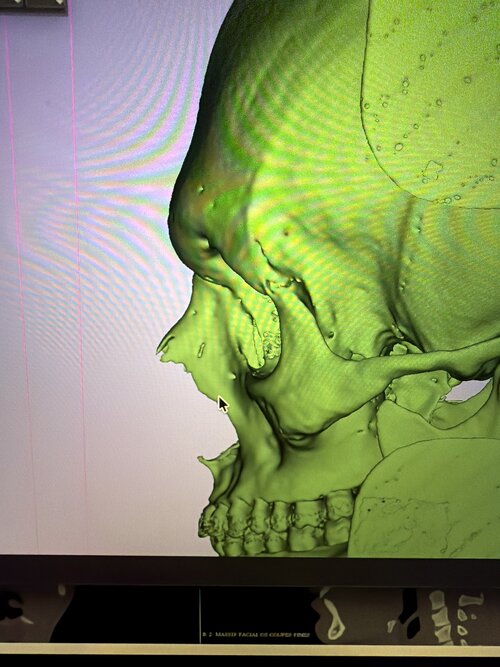

I know I need chin, flared gonian etc. but what else? Specifically I'm worried about my under eye hollows and lack of midface support, is it a soft tissue issue for me or lack of bone? What is the best solution to fix it? Fat grafts? Implants? Some crazy skull splitting procedure?

I have pretty thick skin and what looks like dog shit tier fat distribution, so maybe it's just fat + thick heavy skin sagging into nasolabial folds? Even if that's the case idk what I need. Fat grafts?

Every AI I have asked said I have neutral orbital vector not negative, good maxilla projection xygo projection etc but I feel like it's gaslighting me tbh

I have pretty thick skin and what looks like dog shit tier fat distribution, so maybe it's just fat + thick heavy skin sagging into nasolabial folds? Even if that's the case idk what I need. Fat grafts?

Every AI I have asked said I have neutral orbital vector not negative, good maxilla projection xygo projection etc but I feel like it's gaslighting me tbh